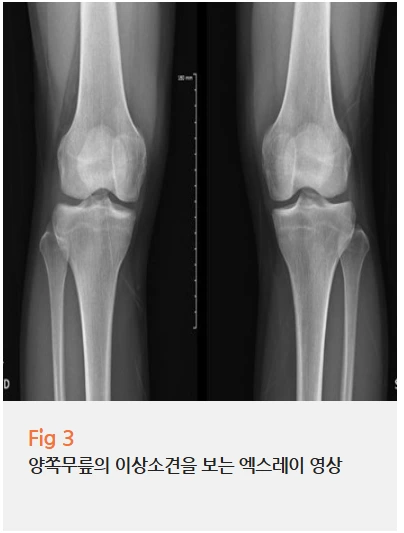

엑스레이와 초음파 검사를 진행했습니다.

검사 결과, 다행히 뼈나 인대에 큰 손상은 없었어요.

하지만 무릎 뒤쪽 슬와부 쪽에 경미한 염증 반응이 관찰됐고,

약간의 삼출액이 고여 있는 상태였습니다.